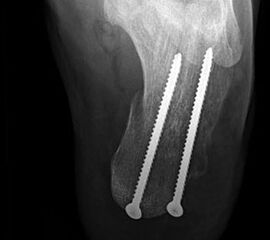

Im Stadium IV der (fixierten) Planovalgus Deformität und lateral betonter OSG-Arthrose umfaßt die operative Therapie eine korrigierende Arthrodese von OSG und USG-Arthrodese (Tibio-talo-calcanear = TTC Fusion) oder bei Arthrose in der Chopart-Gelenkreihe eine pantalare Arthrodese 5556.

Für die TTC-Arthrodese haben sich retrograde Rückfußnägel bewährt, da sie eine gute Primärstabilität bieten und vergleichsweise wenig Weichteildissektion erfordern. Die Indikation muss aber sehr differenziert gestellt werden, zumal das Gangbild anschließend erheblich eingeschränkt sein wird und Anschlußarthrosen trotz optimaler Schuhversorgung mit Abrollrampe zu erwarten sind. Solange die OSG-Arthrose beschwerdearm bleibt, sollte daher auch eine umfangreiche Korrektur der Planovalgus-Deformität mit Rekonstruktion des Ligamentum deltoideum anstelle der TTC- und pantalaren Arthrodese favorisiert werden 57.